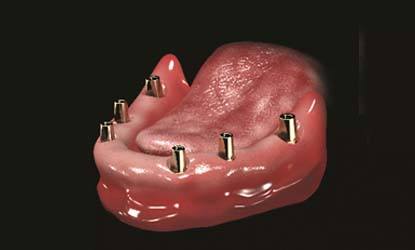

Problema: Trūksta visų dantų

Tikslas:

Pakeisti trūkstamus dantis išimamais protezais (ekonomiškiausias gydymo būdas)

Rezultatas:

Atkurta kramtymo ir estetinė funkcija išimamais dantų protezais